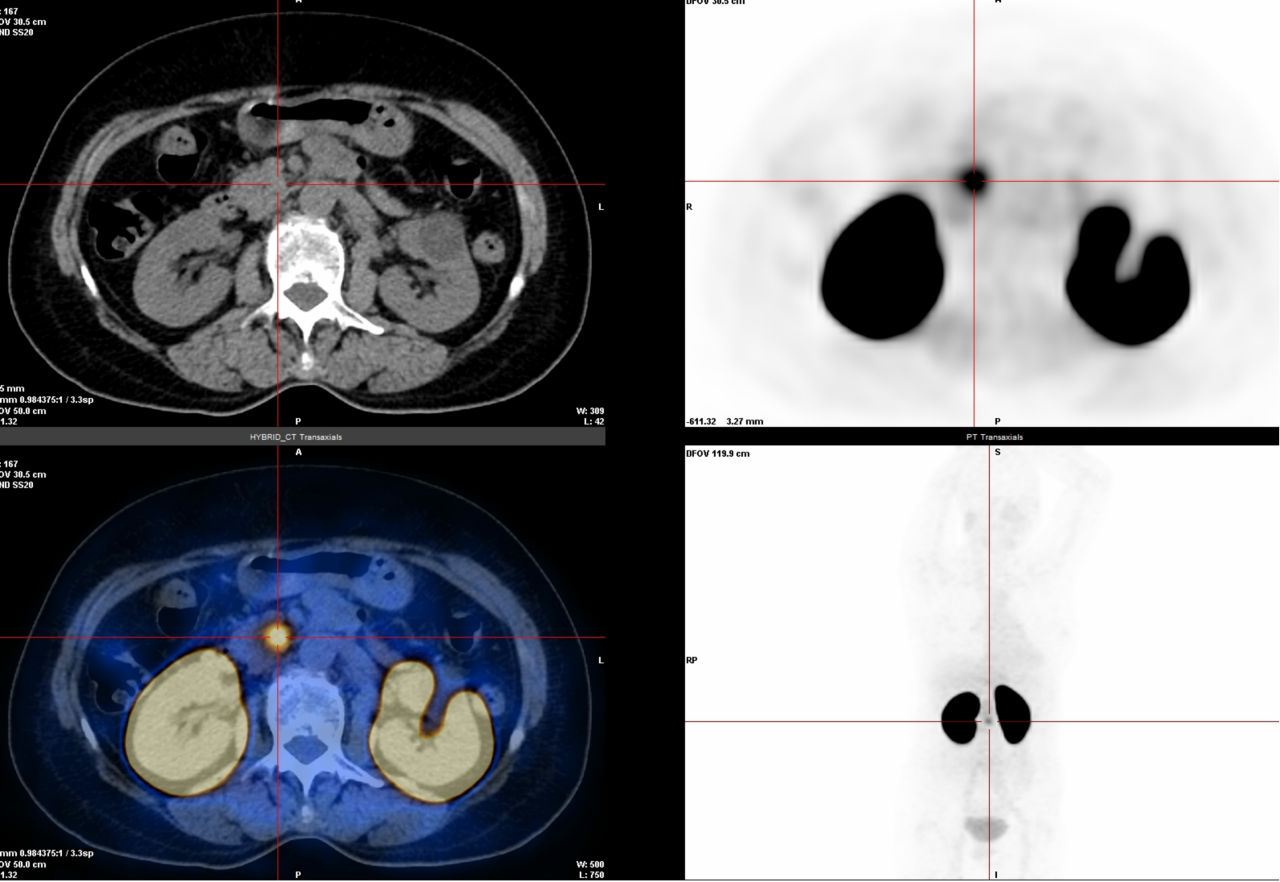

△腹膜转移癌

3.神经内分泌肿瘤检查(68Ga-DOTATATE):专门针对神经内分泌肿瘤(比如某些胃肠胰肿瘤、类癌等),能准确找到肿瘤位置,判断严重程度和治疗效果。